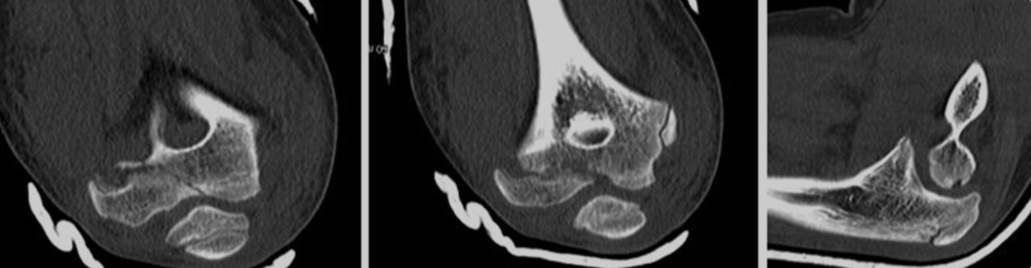

♦ 진단: X-ray,CT,MRI 등 영상의학적 검사를 통해 골절의 위치, 형태, 전위 여부, 성장판 침범 여부 등을 확인합니다. 소아의 뼈는 연골 부위가 많아 성인보다 진단이 어려운 경우가 있습니다.

상완골 외과 골절 : 팔꿈치 바깥쪽(외측과) 골절, 팔을 펴고 넘어질 때 발생, 성장판 손상 위험